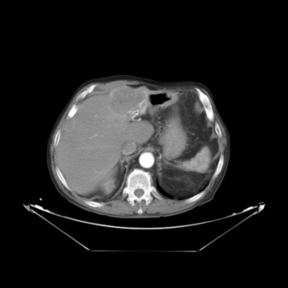

Figure 2. Spatial distances (in millimeters) between corresponding landmarks before and after the registration process

In addition to the previous measurements, the visual outcomes of two of the experiments are shown in Figures 3 and 4, whose purpose is to highlight the most illustrative differences (from a medical point of view) between the results provided by the compared methods. In Figure 3, we observe a normal size of the liver, with discretely irregular contours and homogeneous signal intensity. In hepatic segment II, there is a lesion of 40 mm of maximum axis, encapsulated and with well-defined contours and heterogeneous enhancement in arterial phase (after administration of intravenous contrast), suggestive of hepatocellular carcinoma (HCC). In this slice of the CT scan, we can also observe the aorta that shines in the arterial phase, the lower area of the stomach and the upper area of the spleen. In Figure 4, the liver has a normal size with discretely irregular contours in relation to changes due to chronic liver disease. In hepatic segment IV, a 36 mm diameter focal lesion is identified, which has arterial phase enhancement with a small area of necrosis of 13 mm; it corresponds to a HCC previously chemoembolized with partial necrosis. In this slice of CT, we can also observe the aorta, the gastric chamber and the spleen. When comparing the two methods under study, it can be seen how in Figure 3 the resulting registered datasets are very similar. However, looking closely, it can be noticed that in the right part of the image (left side of the patient) the shape and width of the structures corresponding to the stomach and the spleen in Figure 3(d) match better those in the reference dataset. Likewise, the part of the rib at the upper right of the image is more similar to the same region in the reference dataset by using the proposed method. Regarding the experiment shown in Figure 4, it can be easily appreciated how the geometrical matching (with respect to the reference dataset, Figure 4(a)) of the structures in the right side of the image (specially the gastric chamber) is visually more satisfactory in Figure 4(d). Moreover, the area of tumor necrosis which results from the proposed method is also slightly better aligned.

Arterial phase (reference dataset, R) Non-contrast phase (template dataset, T)

(a) Arterial phase (reference dataset, Failed to parse (MathML with SVG or PNG fallback (recommended for modern browsers and accessibility tools): Invalid response ("Math extension cannot connect to Restbase.") from server "https://mathoid.scipedia.com/localhost/v1/":): {\textstyle R}

)

(b) Non-contrast phase (template dataset, Failed to parse (MathML with SVG or PNG fallback (recommended for modern browsers and accessibility tools): Invalid response ("Math extension cannot connect to Restbase.") from server "https://mathoid.scipedia.com/localhost/v1/":): {\textstyle T}

Registered template, T_u (CR-based method) Registered template, T_u (proposed method)

(c) Registered template, Failed to parse (MathML with SVG or PNG fallback (recommended for modern browsers and accessibility tools): Invalid response ("Math extension cannot connect to Restbase.") from server "https://mathoid.scipedia.com/localhost/v1/":): {\textstyle T_\mathbf{u}}

(CR-based method)

(d) Registered template, Failed to parse (MathML with SVG or PNG fallback (recommended for modern browsers and accessibility tools): Invalid response ("Math extension cannot connect to Restbase.") from server "https://mathoid.scipedia.com/localhost/v1/":): {\textstyle T_\mathbf{u}}

(proposed method)

Figure 3. Visual outcomes of experiment 1 (slice 9): registration of arterial and non-contrast phases of patient 1